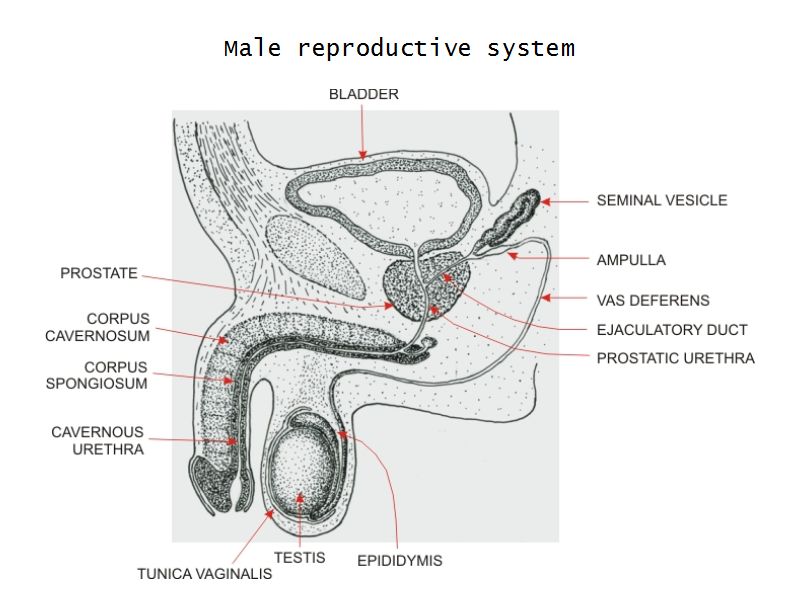

Testis

Slide 84

Testis

- Tunica albuginea

- Lobuli

- Seminiferous tubuli

- Epididymus

- Ductus deferens

Tunica albuginea

- Thick fibrous CT capsule

- Forms septae

- Divide testis into lobuli

Lobuli

- Pyramidal shaped compartments

- Contain 1 - 4 seminiferous tubules each within

- Meshwork of loose CT

- AVN

- Leydig cells

Epididymus

- Long convoluted duct

- With fibrous covering

- Inside visceral layer of tunica vaginalis testis

Ductus deferens

Also vas deferens

Penis

Slide 83Penis

- 3 cylindrical masses erectile tissue

- 2x corpora cavernosa

- 1x corpus spongiosum

- Surrounded by tunica albuginea

- Covered by skin

- Traversed by urethra